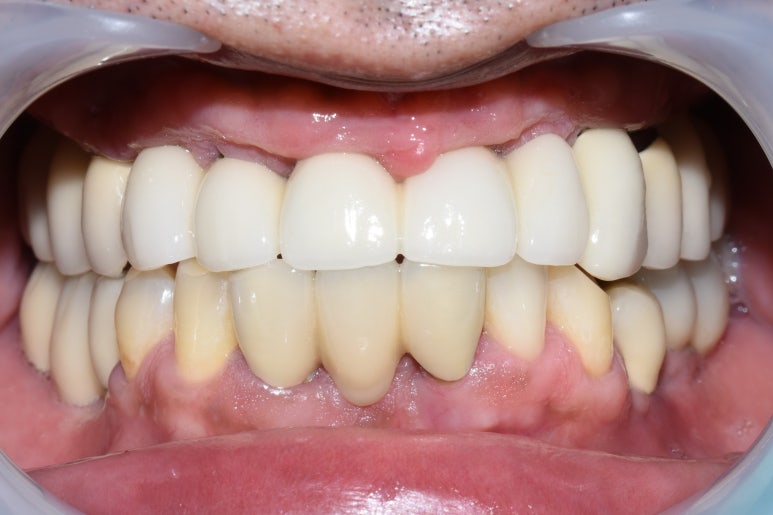

아래는 전후 비교사진입니다.

전 & 후

위의 사진처럼 이제 환하게 웃을 수도 있고, 어금니로 음식도 잘 드실 수 있어서

5kg나 쪘다고 이번 체크 때 말씀해 주셨어요 ^^

환자분이 만족해하시니 저희도 행복해요!